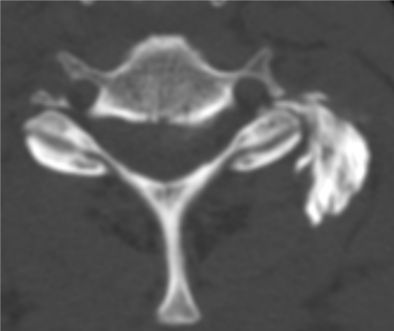

4Infiltration du tendon du tendon 3ième fléchisseur de la main (images 1 et 2) sous contrôle échographique

Images 3 et 4 visibilité du produit anti inflammatoire injecté sous deux incidences orthogonales en regard de la gaine péri tendineuse